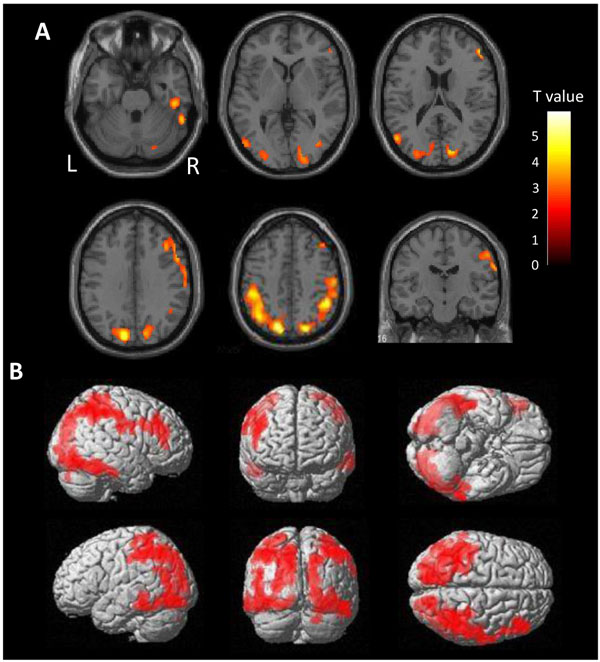

2.8. Voxel-Wise Analysis of [11C]PBB3

Voxel-wise comparison of [11C]PBB3 accumulation data was performed between the ANDE and HC group by 2-sample t-test using SPM12 [60]. In addition, [11C]PBB3 data from individual ANDE case was compared with the HC group by Jack-knife analysis using SPM12 [61]. In both analyses, the threshold for significance was set at P<0.05 Family-Wise Error (FWE)-corrected at a cluster-level following P<0.01 uncorrected at the voxel level.

3.2. Tau Accumulation in ANDE

There is a very high burden of tau in the diffuse area of the bilateral parietal lobes in ANDE by voxel-wise comparison with HC (Fig. 2). Mild accumulation was found in the frontal lobes and lateral temporal lobes on both sides. Accumulation in the cortices neighboring the sagittal sinus and the transverse sinus may reflect spillover of nonspecific accumulation in the sinuses. Cortical accumulation was observed to be centered on the gyrus, not on the sulcus, excluding the possibility of vascular spillover on the cortex.